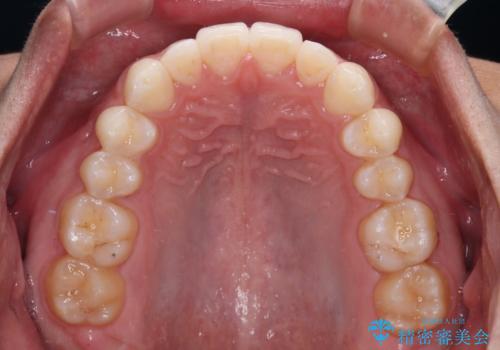

前歯のデコボコとクロスバイト インビザライン矯正治療

上下顎ともに歯列全体の側方拡大を行い、下顎前歯はIPR(歯と歯の間を削る)によってデコボコとクロスバイトが解消するように設計し、インビザラインにより治療を行うこととしました。

2年弱で終了する予定でしたが、途中来院されなかった時期があり、その後舌側転位している前歯を動かせるところまで動かしたいとのことで4年ほど治療を継続されました。